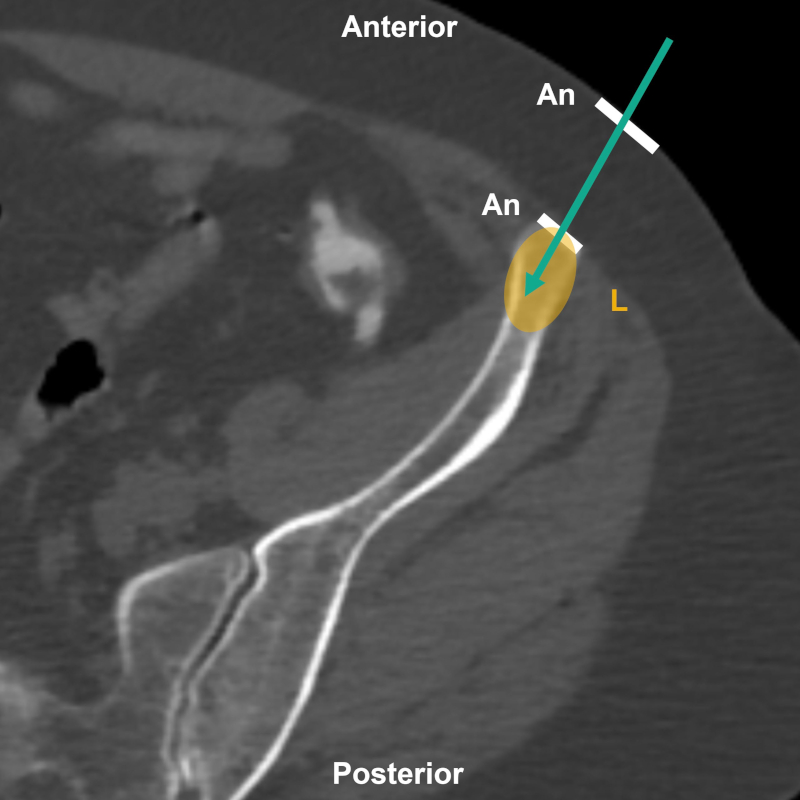

Existen dos técnicas básicas para la toma de muestra: directa (Fig. 1) o coaxial (Fig. 2). En la primera, la aguja se introduce directamente en la lesión para la obtención de material biológico5. En la segunda, se introduce una aguja que sirve como guía hasta la lesión, y por dentro de esta se introduce otra aguja más fina para la obtención de material. Este último mecanismo permite el acceso seguro a la lesión, disminuyendo el número de punciones requeridas, el disconfort del paciente, la duración del procedimiento, el riesgo de siembra tumoral y las posibilidades de sangrado. Su uso está particularmente indicado para biopsias de lesiones profundas5,6,7. Ante una hemorragia, es posible utilizar agentes embolizantes mediante la aguja introductora6. En nuestra experiencia, la técnica coaxial se utiliza cuando debemos biopsiar un tumor en la cavidad pelviana, una lesión ósea endomedular de baja densidad con cortical indemne, en lesiones profundas respecto al plano cutáneo o cuando se requiere hacer una biopsia transósea.

Figura 1

Esquema sobre TC, corte axial de hueso ilíaco izquierdo, para BP directa. Aguja (flecha), sitios de infiltración anestésica (An) y lesión (L).